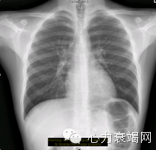

半年后复查:心脏缩小,心功能好转。

正规治疗2年后随访:

• 2年后复查:心衰症状缓解,影像学提示心脏结构及功能恢复正常